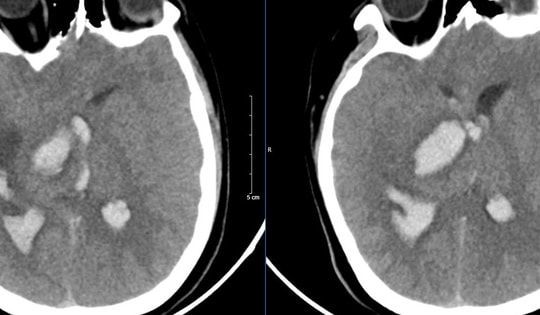

Bệnh nhân 15 tuổi tử vong sau khi bị đau đầu đột ngột, bác sĩ cảnh báo các dấu hiệu cần đến bệnh viện ngay

Bị đau đầu, tê hoặc yếu tay chân, người bệnh được đưa đến viện nhưng vẫn tử vong hoặc cứu được thì cũng để lại di chứng nặng nề nguyên nhân là do dị dạng mạch máu não.

Bệnh viện Bạch Mai cứu sống cụ ông 103 tuổi bị đột quỵ cao tuổi nhất từ trước đến nay

GĐXH – Theo các bác sĩ, với các ca đột quỵ thông thường, việc đưa ra phác đồ tiêu huyết khối kết hợp với can thiệp mạch không phải là điều khó khăn. Tuy nhiên, việc áp dụng cả 2 phương pháp này trên bệnh nhân 103 tuổi là một thách thức vô cùng lớn.